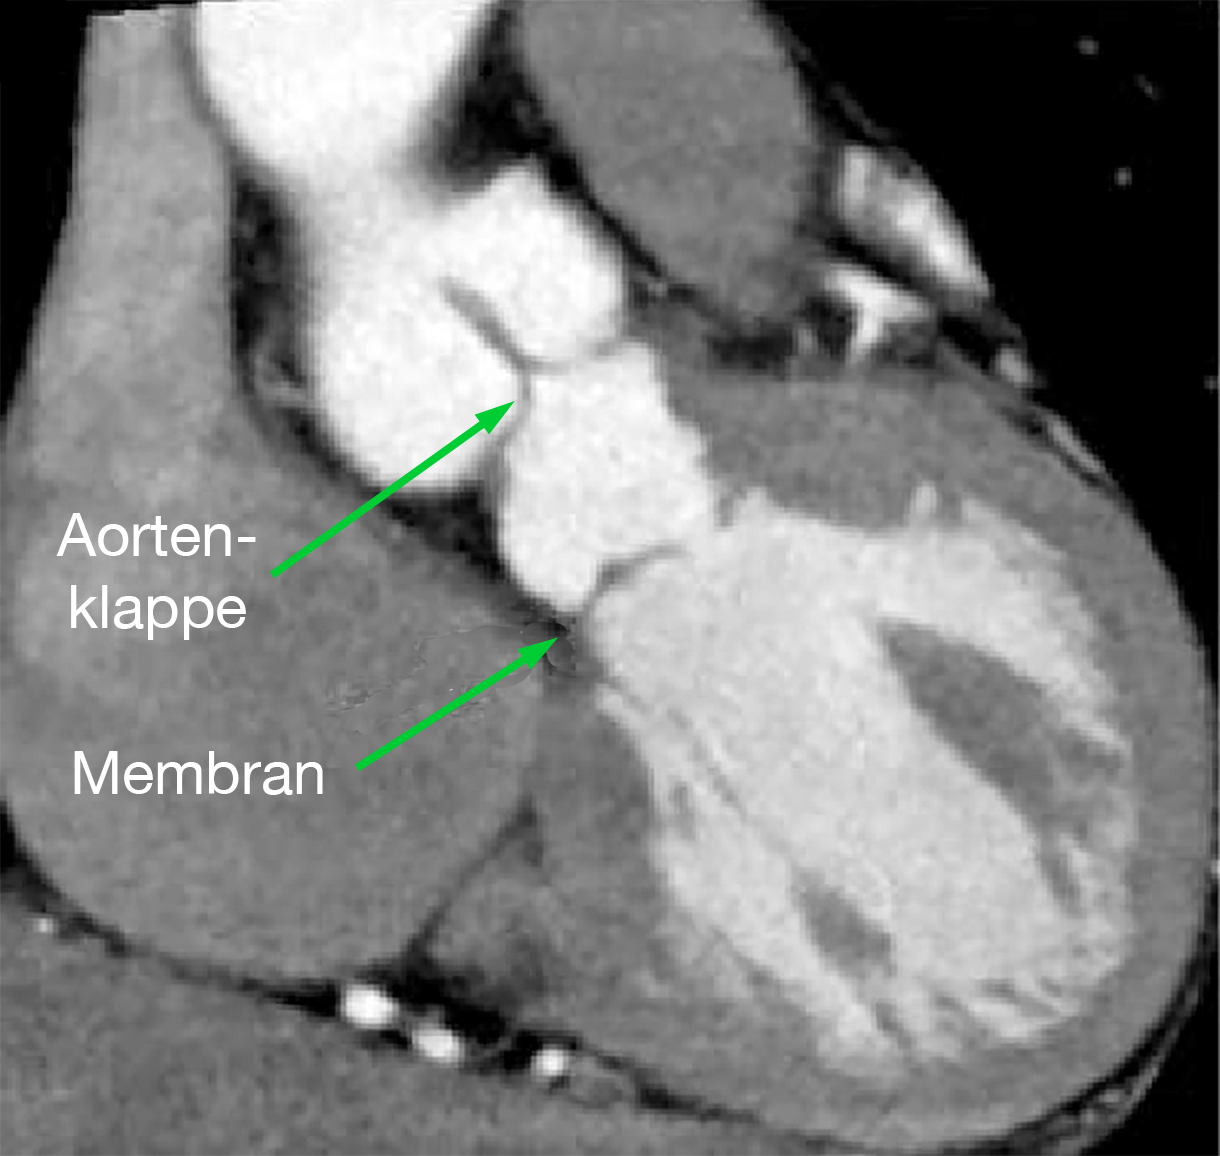

|  |  |

| Abb. 25 | Abb. 26 |

| Supravalvuläre Aortenstenose (Pfeil) im MRT | Membranförmige subvalvuläre Aortenstenose im MRT |

Die MRT-Untersuchung spielt in der Diagnostik eine eigentlich nur untergeordnete Rolle, denn prinzipiell liefert sie dieselben Ergebnisse wie das Echo (Abb. 25 und 26).